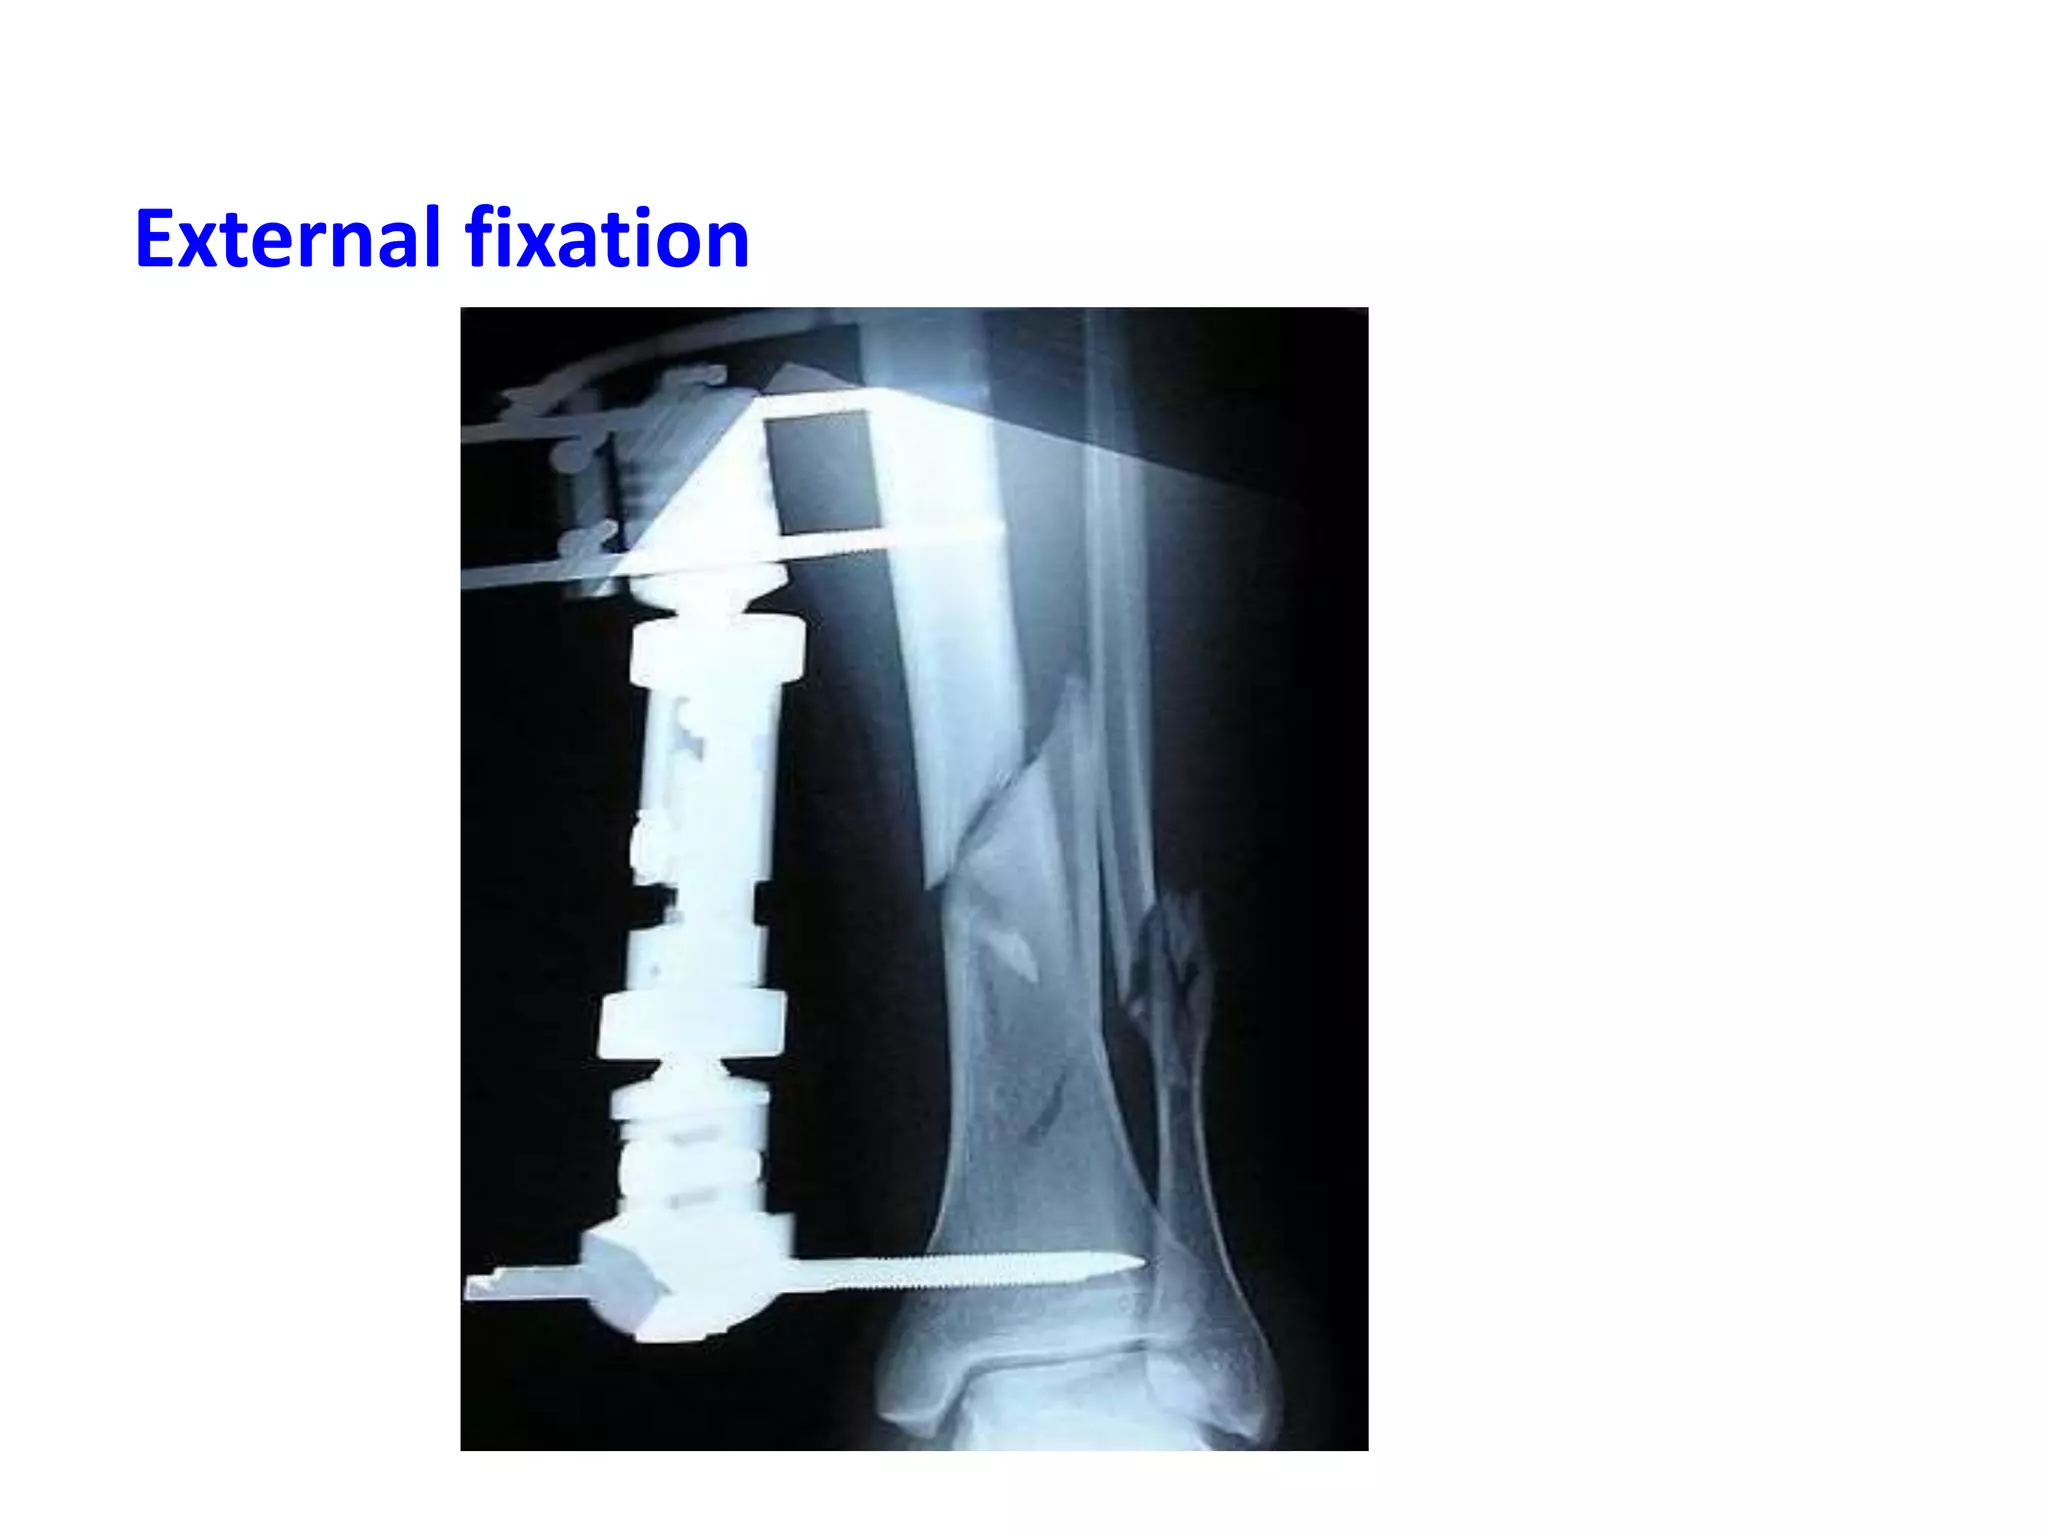

External fixation

Methods of relativestability Bridging plate